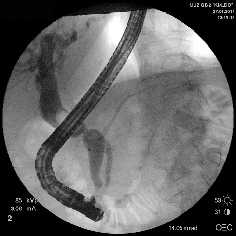

Рубцовая стриктура средней трети холедоха, холедохолитиаз

Полный блок средней трети холедоха (клипса на холедохе)

Несостоятельность культи пузырного протока

Рис. 1. Рентген-фото выявленной патологии

Rg-фото. Бужирование стриктуры холедоха

Rg-фото. Баллонная дилятация стриктуры холедоха

Rg-фото. Стентирование холедоха

Рис. 2. Наиболее часто выполняемые эндоскопические вмешательства